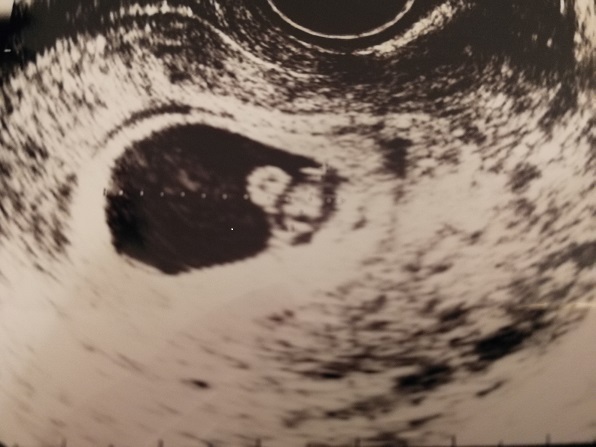

7週0日(7w0d・男の子)|るちゃんHA さん(22歳)

エコー写真撮影時のエピソード:月経がこず、ストレスできてないだけかと思いきや、妊娠検査薬を使用したら陽性反応が出たのでその翌日に病院に行き、内診してもらったところ、卵が2つあるよと言われ、双子だと思う。と言われてとてもびっくりしました。その日にちゃんと心音も聞けました。